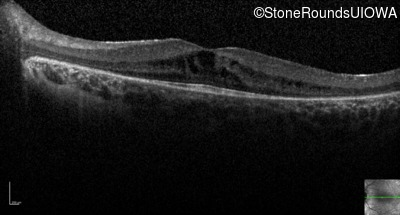

Optical Coherence Tomography - Right - 20/40 -2

Exemplar / OCT Stack

OCT Stack